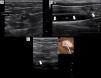

Briefly, with a tourniquet high in the arm, we scan for target veins based on their patency, size and depth. Patent veins with a diameter ≥4mm and closest to the skin are only considered for cannulation (Fig. 2a). Basilic vein of the arm, a brachial vein or the cephalic vein of the arm typically fulfill these criteria. For catheter placement, aseptic technique and maximal sterile barrier precautions are used. We perform the in-plane technique in all the cannulations. As in our institution there are no available kits of MC, we replace it by a central venous catheter kit (polyurethane-based, 14-16G, 20–30cm in length catheters). After inserting the needle by dynamic ultrasound guidance, blood is freely aspirated and guidewire is then passed, we confirm that the latter is in the vein lumen before passing the dilator (Fig. 2b). When introducing the catheter, to avoid advancing in the subclavian vein, we check by ultrasound that the catheter tip lies in the thoracic tract of the axillary vein (Fig. 2c). To avoid dislodgement of the catheter, we secure it by suturing both the holding clips and the hub to the skin.

Midline catheter (16G, 20cm in length) placed in the left arm of a critical care patient with COVID-19. On the right, a yellow line is illustrating the catheter path and the position of the tip in the axillary region (axillary vein). Modified from Blanco P. The midline venous catheter. Rev Hosp Emilio Ferreyra. 2021; 1(1):e3–e9. http://revista.deiferreyra.com/index.php/RHEF/article/view/31/89. (CC BY 4.0).